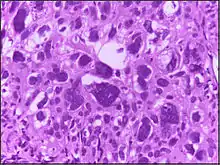

![]() | Renal cell carcinoma | Micrograph of clear cell renal cell carcinoma showing cells with clear cytoplasm, typically arranged in nests and nuclear atypia. | Category: Histopathology of renal cell carcinoma | Renal cell carcinoma |